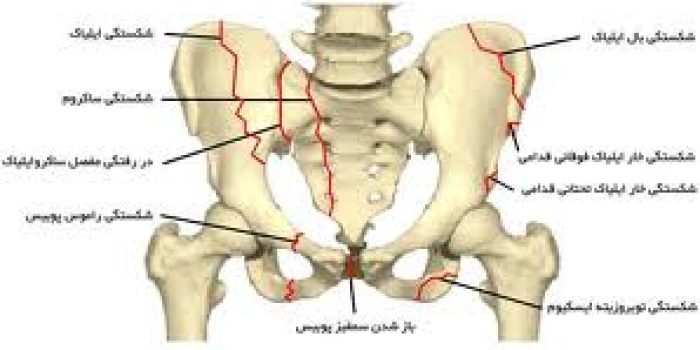

آسیب های حلقه لگن Pelvic ring injuries جزئی از یک دسته بزرگتر به نام شکستگی های لگن بوده و ممکن است بصورت شکستگی یا دررفتگی و یا ترکیبی از شکستگی و دررفتگی باشند. این آسیب ها را میتوان به دو دسته کلی آسیب های پایدار و ناپایدار تقسیم کرد.

آسیب های پایدار حلقه لگن

این گروه از آسیب ها شامل شکستگی هایی هستند که شکل حلقوی لگن را تغییر نمیدهند. این شکستگی ها معمولا بر اثر ضربات با شدت کم بوجود آمده و عوارض شدیدی ندارند.

انواع این شکستگی ها عبارتند از

- شکستگی خار ایلیاک فوقانی قدامی

- شکستگی خار ایلیاک تحتانی قدامی

- شکستگی توبروزیته ایسکیوم

- شکستگی بال ایلیاک

- شکستگی راموس پوبیس

آسیب های ناپایدار حلقه لگن

آسیب هایی که موجب میشوند حلقه لگن از یک یا چند محل باز شود. این دسته از آسیب ها شدیدترند و موجب بروز مشکلات بیشتری برای بیمار میشوند.

در غالب این آسیب ها حلقه لگن در دو ناحیه جلو و عقب باز میشود. باز شدن حلقه لگن در جلو ممکن است بصورت شکسته شدن راموس های پوبیس یا باز شدن سمفیز پوبیس (محل اتصال دو استخوان بی نام در جلو) باشد.

آسیب و باز شدن حلقه لگن در عقب میتواند به سه صورت ایجاد شود:

- شکسته شدن استخوان ایلیوم

- دررفتگی مفصل ساکروایلیاک (مفصل بین استخوان بی نام و ساکروم)

- شکسته شدن استخوان ساکروم